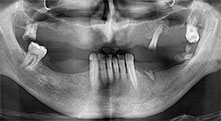

residual dentition

A 40-year-old patient with very poor residual dentition wanted an implant-based restoration. Because he is a smoker, a sinus lift in the maxilla with a fixed denture was contraindicated. A bar denture on four anterior implants was planned.

Piezomed B6

The alveolar ridge was split on both sides by piezo surgery (instrument: Piezomed B6). The implants were placed in the same procedure and the peri-implant bone was additionally built up using the GBR technique.

Implants

The four implants are in situ, as planned. The distal maxillary molars can still be used to fix the lined denture, which was introduced one month after implantation.